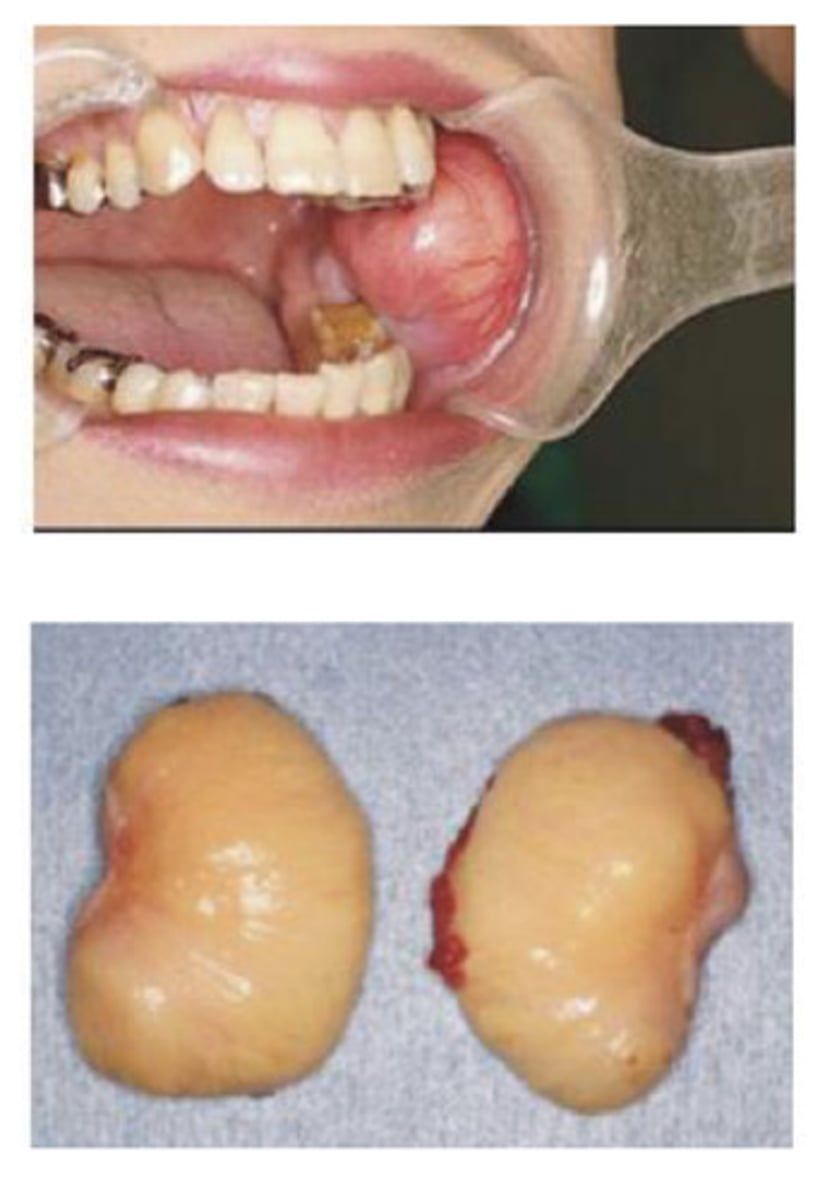

Denture hyperplasia

What is this?

Associated with chronic irritation - treatment is excision and creation of a new applicance

An adenoma

A benign tumor of glandular origin - usually lobulated firm or rubbery and can be pleomorphic or monomorphic

Adenoma